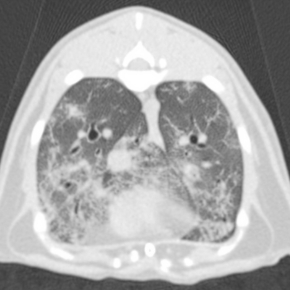

As a general rule if a heart murmur is quiet (grade 1-2/6), localised, short (does not persist all the way through systole) or variable (varies or disappears at different heart rates) then it is less likely to be associated with structural defect, BUT we simply cannot be sure. A murmur only tells us there is turbulent flow in the heart, it is not a diagnostic test. So if the murmur persists, then a definitive diagnosis is vitally important and this can only be done with a full Doppler echocardiogram (cardiac ultrasound scan).

All of our cardiologists use high quality cardiac ultrasound machines, and are trained to perform a full echocardiogram to specialist standard. We perform a full consultation and clinical examination, and will report the results of the scan immediately afterwards to the owner with a thorough discussion. We ensure they are fully informed and understand any possible treatment options or future risks for their pet. In some cases such as PDA or pulmonic stenosis, we can perform keyhole cardiac surgery to permanently fix the problem, or significantly improve it so that the puppy may lead a normal life, but it is very important to catch these early for the best outcome.